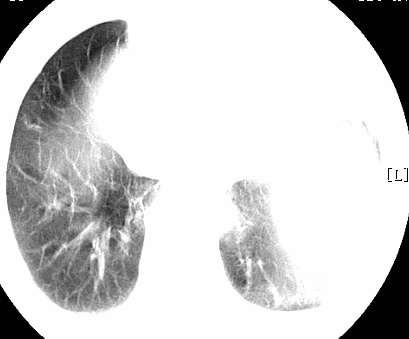

标题: CT26680:肺部右下肺静脉干结节的界定 [打印本页]

标题: CT26680:肺部右下肺静脉干结节的界定

经追查说有支扩咯血病史,但不确定

考虑1、周围型肺癌,2肺静脉畸形,前者可能大,建议增强检查。

考虑1、周围型肺癌,2肺静脉畸形,前者可能大,建议增强检查。支持!

不排除右肺下叶周围型肺癌可能。